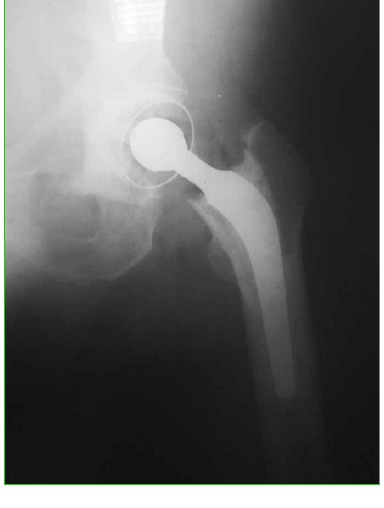

Reemplazo total de cadera en un paciente con amputación supracondílea homolateral